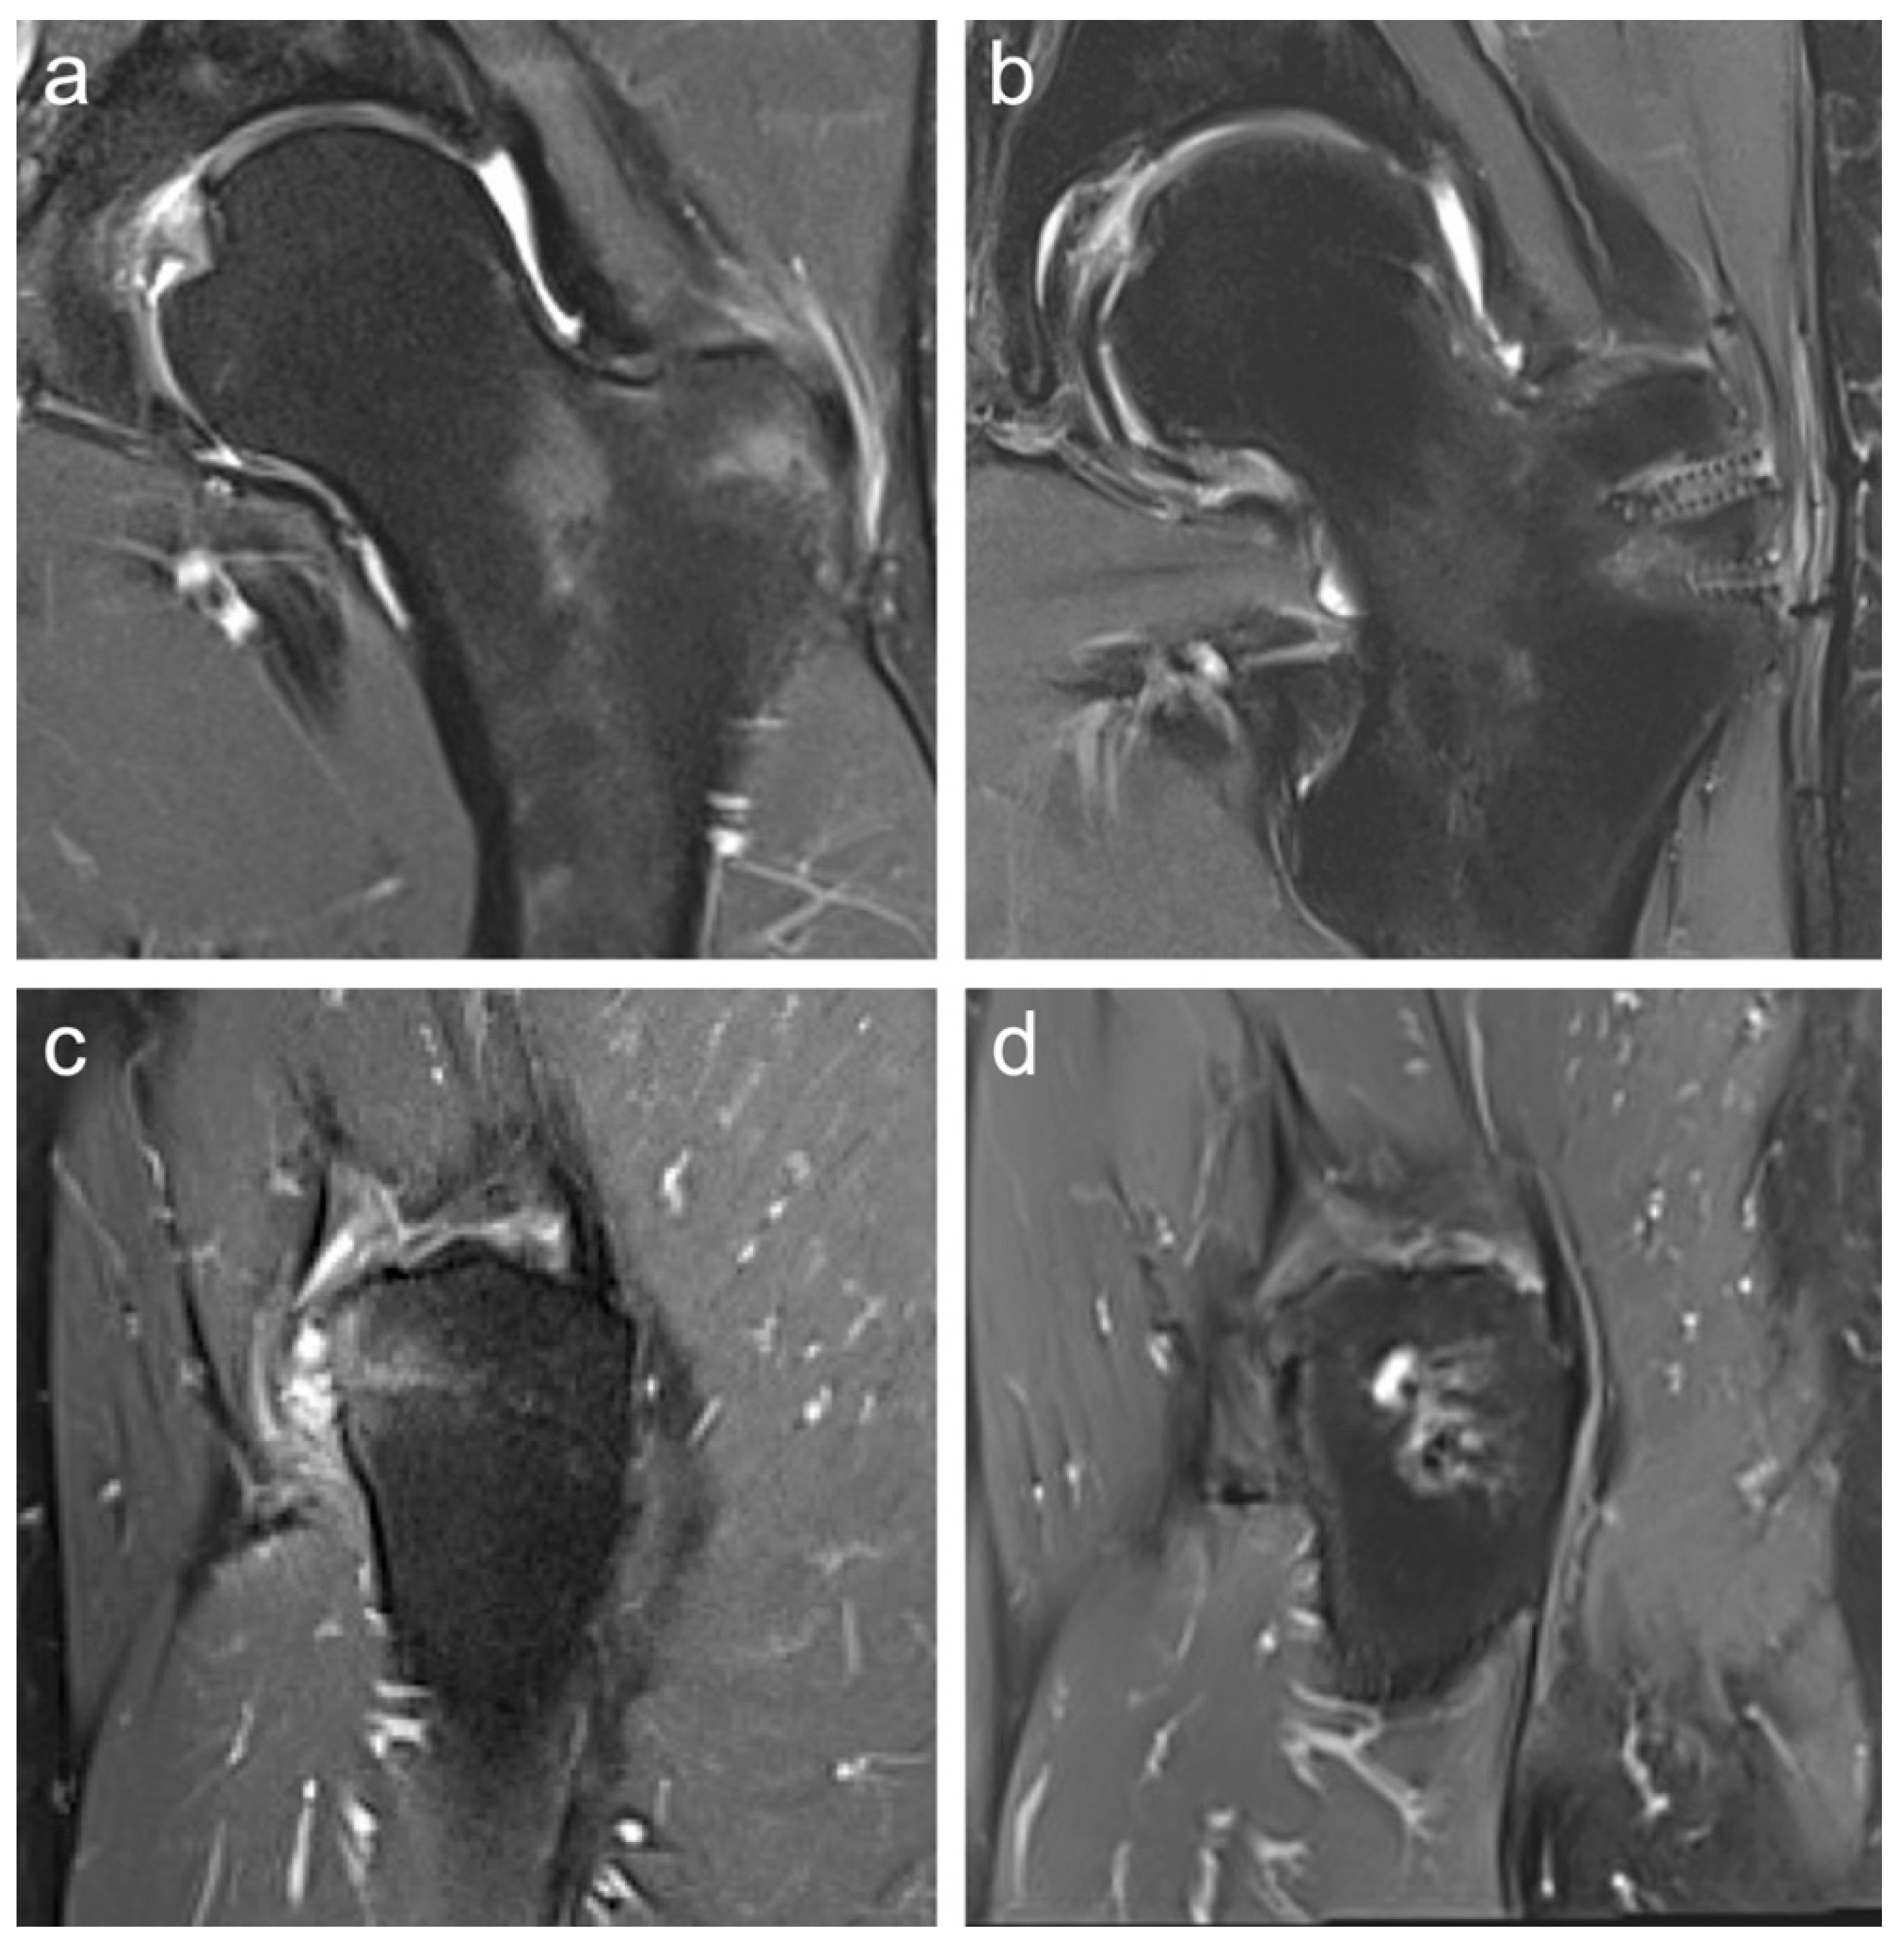

Preoperative imaging included 3-Tesla magnetic resonance imaging (MRI) (Figure 1a,c) and standard radiographs in all patients to confirm the diagnosis, assess muscle quality, and exclude other pathologies such as isolated trochanteric bursitis without involvement of the gluteal tendon footprint. Postoperative MRI was performed to confirm the integrity of the suture anchors, verify tendon reattachment at the gluteal footprint, and rule out re-rupture, seroma, or recurrent bursitis (Figure 1b,d).

Figure 1. Preoperative coronal (a) and sagittal (c) 3-Tesla MRI showing a partial rupture of the GMin and GMed tendon insertions at the greater trochanter. Postoperative coronal (b) and sagittal (d) 3-Tesla MRI confirm intact suture anchor placement, complete tendon reattachment, and absence of re-rupture, seroma, or recurrent bursitis.